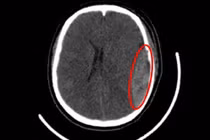

Qua thăm khám và chẩn đoán hình ảnh, các bác sĩ xác định bệnh nhân bị đa chấn thương nặng, bao gồm: chấn thương sọ não nặng hôn mê sâu, chấn thương hàm mặt, chấn thương ngực kín với gãy nhiều xương sườn, tràn máu khoang màng phổi, kèm tổn thương gan và thận. Trước phẫu thuật, người bệnh hôn mê sâu, đồng tử hai bên giãn tối đa, mất hoàn toàn phản xạ ánh sáng – dấu hiệu cho thấy tổn thương não cực kỳ nghiêm trọng, tiên lượng rất xấu.

Trước tình trạng nguy kịch, BS.CKII Hoàng Chí Thành – Phó Giám đốc Bệnh viện cùng BS.CKII Mạc Hoàng Dương – Trưởng khoa Ngoại Thần kinh đã trực tiếp thăm khám, hội chẩn khẩn và quyết định phẫu thuật cấp cứu mở hộp sọ, lấy máu tụ, cầm máu và giải tỏa chèn ép não. Mặc dù hy vọng sống sót rất mong manh, nhưng với tinh thần trách nhiệm cao nhất, toàn bộ ê-kíp y tế Khoa Cấp cứu, Khoa Phẫu thuật - Gây mê hồi sức và Khoa Ngoại Thần kinh đã khẩn trương phối hợp triển khai phẫu thuật. Chỉ trong vòng 15 phút kể từ khi có kết quả chụp CT, bệnh nhân được chuyển thẳng vào phòng mổ.

Trong quá trình phẫu thuật, ThS.BS Nguyễn Văn Khoa, khoa Ngoại thần kinh cùng ê-kíp ghi nhận khối máu tụ lớn chèn ép nhu mô não, tổn thương dập não phức tạp, kèm chảy máu từ nhiều nguồn. Ca mổ kéo dài hơn 2 giờ trong điều kiện hết sức căng thẳng. Nhờ kinh nghiệm và sự phối hợp nhịp nhàng, kíp phẫu thuật đã kiểm soát được nguồn chảy máu và giải phóng chèn ép não, giành lại sự sống cho người bệnh. Sau phẫu thuật, bệnh nhân được an thần, thở máy và theo dõi chặt chẽ. Những dấu hiệu hồi phục tích cực sớm xuất hiện khi đồng tử hai bên co lại, có phản xạ ánh sáng.

Kỳ tích cứu sống thành công bệnh nhân chấn thương sọ não nặng. Ảnh BV